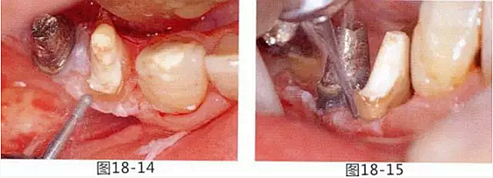

圖18-14 使用圓頭金剛車針進行骨外科處理。

圖18-15 使用鎢鋼車針去除殘留在牙根面的纖維。

圖18-16,17 確認是否有殘留的骨組織缺損。

圖18-18 與頰側(cè)一樣,舌側(cè)也固定在骨膜上,使齦瓣上端確定在牙槽嵴頂。